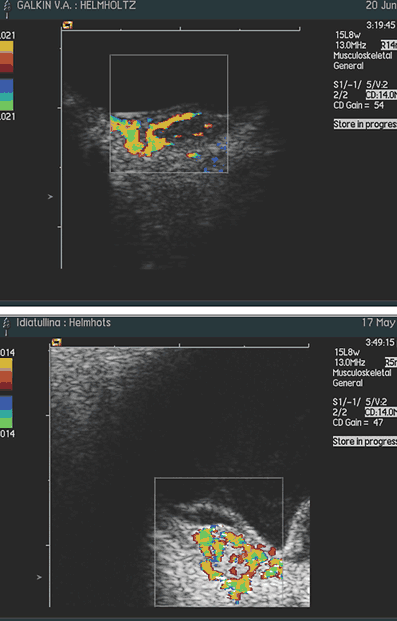

Рис. 2. Распределение больных с учетом локализации С учетом локализации опухоли ранним признаком ее, заставившей больных обратиться к офтальмологу, практически во всех случаях явилось снижение зрения. К моменту обследования гемангиома имела толщину, равную в среднем 3±0,7 мм (от 1,6 до 3,9 мм), а основание ее достигало в среднем 8,9±3,2 мм (от 3,8 до 13,5). Во всех случаях имелась вторичная отслойка сетчатки (в 6 случаях плоская, в 3–х – высокая). При УЗ–сканировании у всех больных определялся проминирующий гиперэхогенный очаг без «экскавации» хориоидеи с ровной поверхностью. При исследовании в режиме ЦДК во всех случаях, независимо от размеров отграниченной гемангиомы, выявлено равномерное распределение новообразованных сосудов по всей ее толщине и площади. Визуально кровоснабжение гемангиомы осуществляется за счет сосудов хориоидеи: сосуды сетчатки не участвуют в ее питании (рис. 3, 4) Только при юкстапапиллярной локализации (3 случая) опухоль получала двойное кровоснабжение – за счет сосудов хориоидеи и ЦАС (рис. 5).

Рис. 3, 4: Цветовое допплеровское картирование гемангиомы макулярной локализации